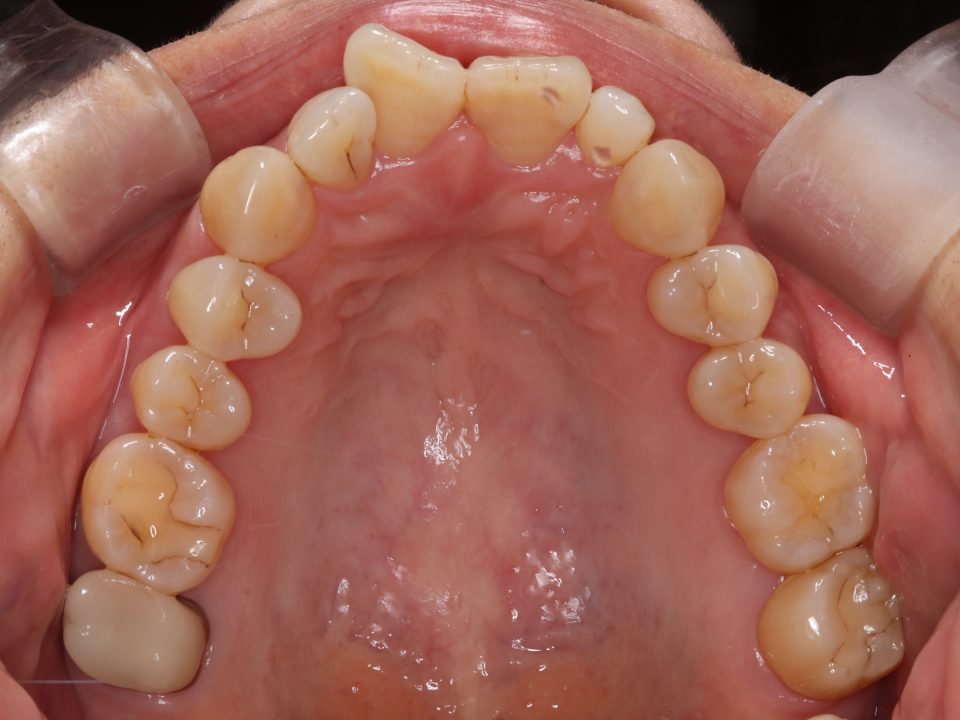

矯正治療前

40代女性の患者さんです。

上の前歯が曲がっていることが気になり矯正治療を始めました。

マウスピース型の矯正治療装置を使用し、歯のやすり掛け(IPR)を行いました。